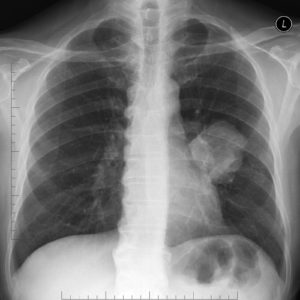

Проводится обзорная флюорография или рентгенография легких в двух проекциях – передней и боковой. Лучшее качество изображения получается при использовании цифровых аппаратов. Многое зависит и от установки пациента. Поэтому при выполнении снимков следует точно выполнять все рекомендации рентгенлаборанта. Это обеспечит более четкое изображение.

По данным рентгенографии определяют локализацию опухоли в доле и/или сегменте легкого.

В начале роста опухоли она лишь незначительно сужает его просвет. Поэтому на снимке определяется либо норма, либо снижение прозрачности ткани сегмента, усиление в нем легочного рисунка.

При дальнейшем сужении бронха опухоль вызывает образование эмфиземы (вздутия) легкого в соответствующем сегменте. Это проявляется повышенной воздушностью легочной ткани и обеднением легочного рисунка.

Когда бронх полностью перекрывается, вентилируемый им участок легкого спадается. Возникает ателектаз. На рентгенограмме он выглядит как интенсивная треугольная тень. При поражении доли или всего легкого определяется тень большого размера.